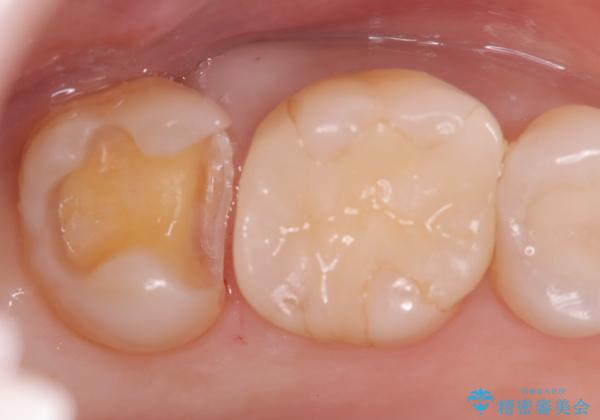

- 昔入れたメタルインレーの下にむし歯が再発したため治療を行った患者様です。

メタルインレーは汚れが付着しやすく、適合も悪いことがあるため、むし歯が再発しやすかったと思われます。

フロスなどの日常の清掃はもちろん不可欠ですが、メタルインレーより汚れが付着しずらいセラミックインレーにて今回は治療を行いました。

セラミックインレー装着時はラバーダムを使用して行っています。